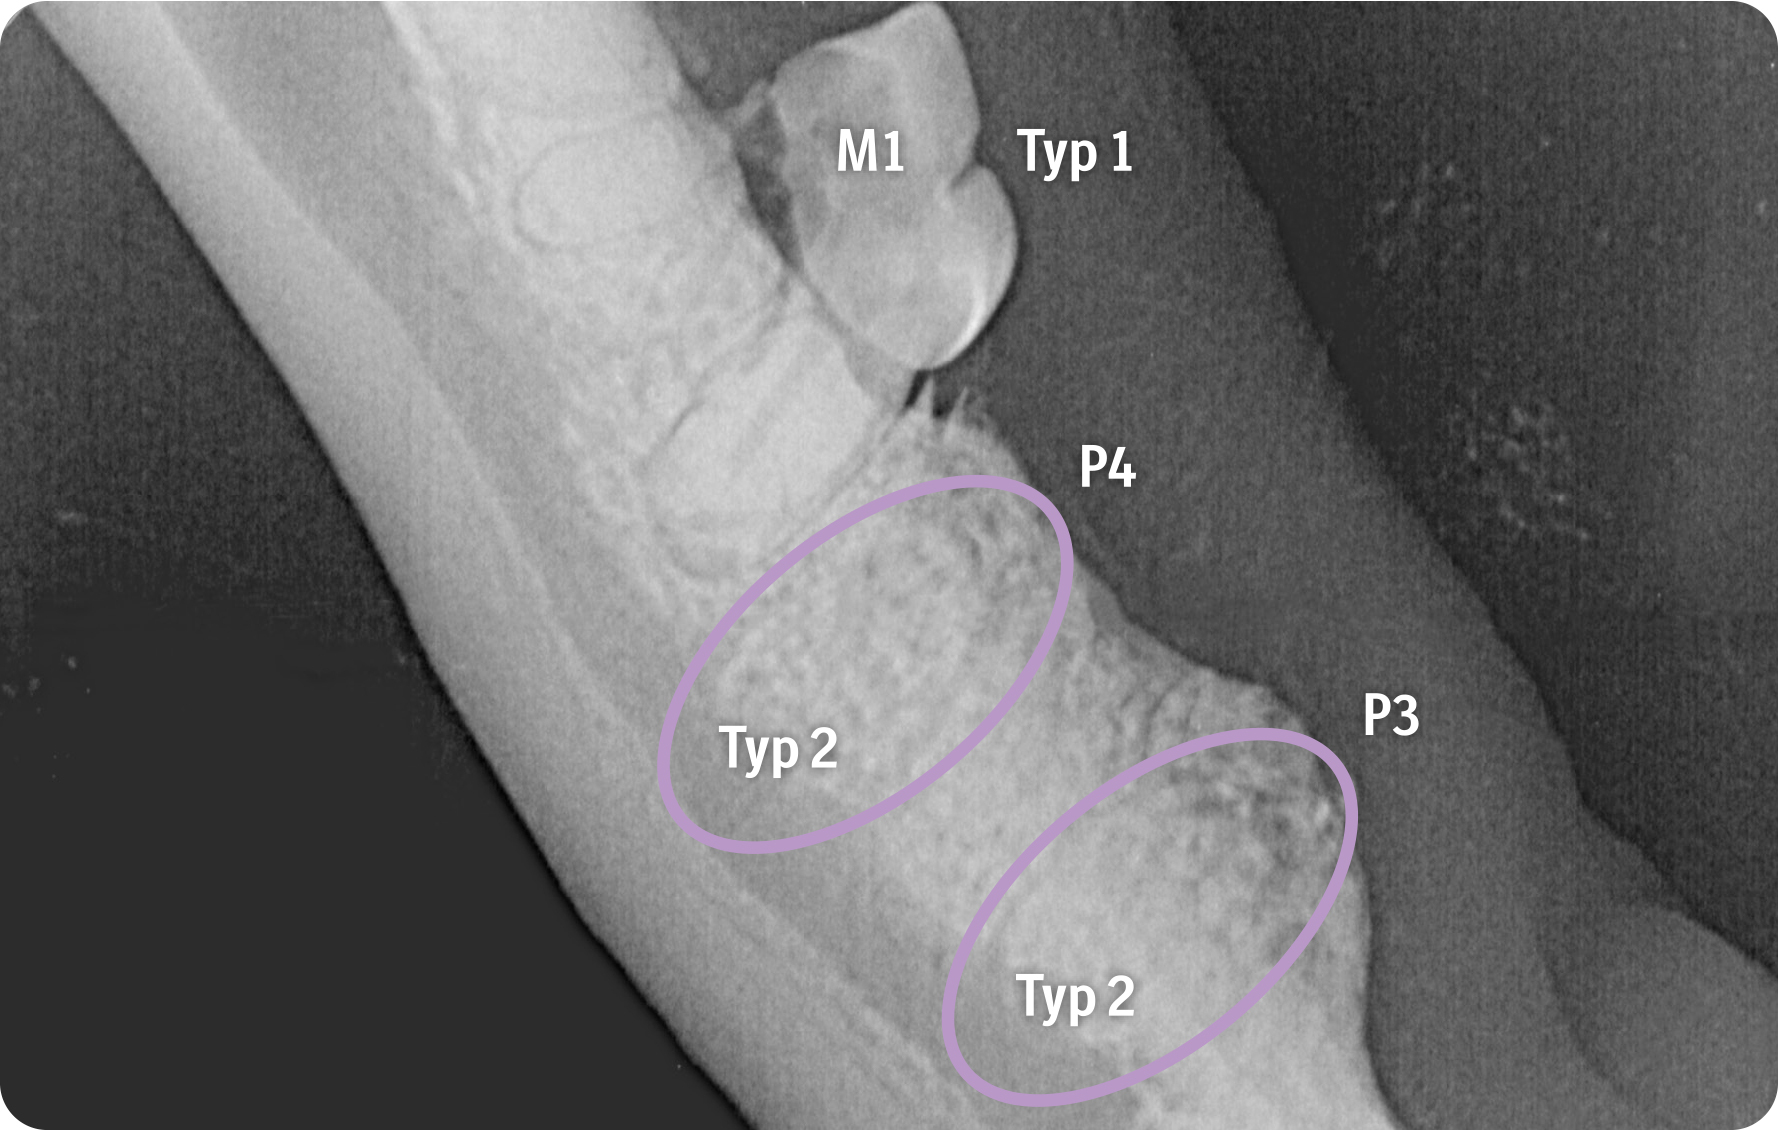

Über entsprechende Röntgenbefunde kann die Zahnresorption aufgezeigt werden. Durch die Visualisierung des Kalenders haben Tierärzt:innen ein gutes Medium, um zu erreichen, dass ihre Botschaft von Tierhalter:innen nicht nur gehört, sondern auch verstanden wird. Wichtig dabei ist die Unterscheidung der einzelnen Typen der Erkrankung. Die intraorale Aufnahme des Unterkiefers rechts zeigt eine Zahnresorption Typ 1 bei M1 mit fokaler Zahnresorption im Kronenbereich sowie den Übergang zur Wurzel bei erhaltenem Parodontalspalt. Bei P3 und P4 werden durch die Aufnahme fehlende Kronenbereiche mit nur noch schwach nachvollziehbaren resorbierten und in Knochengewebe umgebauten Wurzeln erkennbar sowie der Verlust des Parodontolspalts, also eine Zahnresorption vom Typ 2.

Die Bildgebung zeigt, wie unterschiedlich Zahnresorptionen bei der Katze im Röntgen aussehen können. Wichtig für die Praxis zu wissen ist, dass sie je nach Typ unterschiedlich behandelt werden müssen: So ist eine Kronenamputation nur bei einer Typ-2-Zahnresorption mit vollständigem Verlust des Parodontalspalts möglich. Bei Zahnresorption Typ 1, also bei einem erhaltenen Parodontalspalt, müssen alle Wurzeln extrahiert werden.